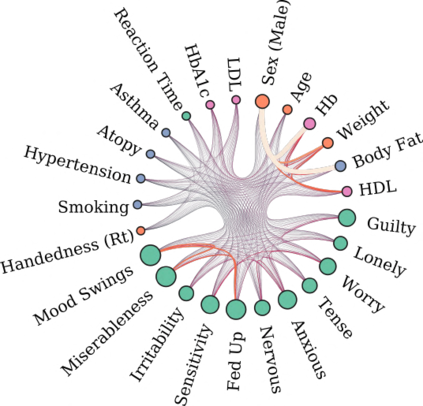

Our knowledge of the organisation of the human brain at the population-level is yet to translate into power to predict functional differences at the individual-level, limiting clinical applications, and casting doubt on the generalisability of inferred mechanisms. It remains unknown whether the difficulty arises from the absence of individuating biological patterns within the brain, or from limited power to access them with the models and compute at our disposal. Here we comprehensively investigate the resolvability of such patterns with data and compute at unprecedented scale. Across 23 810 unique participants from UK Biobank, we systematically evaluate the predictability of 25 individual biological characteristics, from all available combinations of structural and functional neuroimaging data. Over 4526 GPU hours of computation, we train, optimize, and evaluate out-of-sample 700 individual predictive models, including fully-connected feed-forward neural networks of demographic, psychological, serological, chronic disease, and functional connectivity characteristics, and both uni- and multi-modal 3D convolutional neural network models of macro- and micro-structural brain imaging. We find a marked discrepancy between the high predictability of sex (balanced accuracy 99.7%), age (mean absolute error 2.048 years, R2 0.859), and weight (mean absolute error 2.609Kg, R2 0.625), for which we set new state-of-the-art performance, and the surprisingly low predictability of other characteristics. Neither structural nor functional imaging predicted psychology better than the coincidence of chronic disease (p<0.05). Serology predicted chronic disease (p<0.05) and was best predicted by it (p<0.001), followed by structural neuroimaging (p<0.05). Our findings suggest either more informative imaging or more powerful models are needed to decipher individual level characteristics from the human brain.